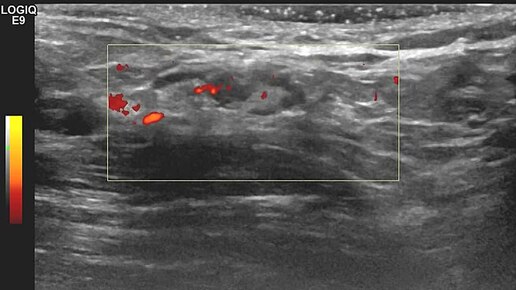

Видео к статье: "Микрометастаз" в лимфатическом узлеhttps://dzen.ru/a/aD_vEeN4BUINS3HY

Ультразвуковые находки от врача УЗД Зорина Я.П.